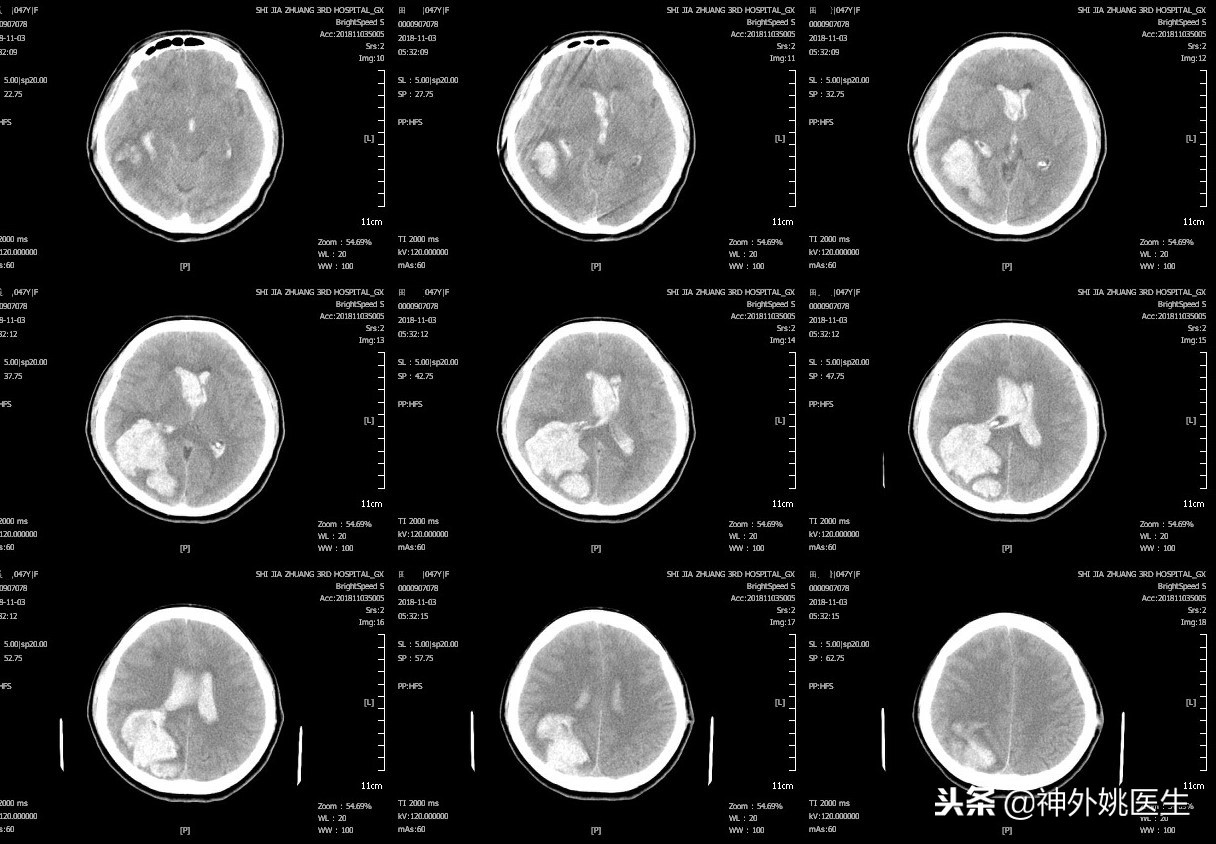

头CT检查:右颞顶枕血肿,破入脑室及蛛网膜下腔;脑干受压密度减低;右额叶陈旧梗死灶。(图1)

图1